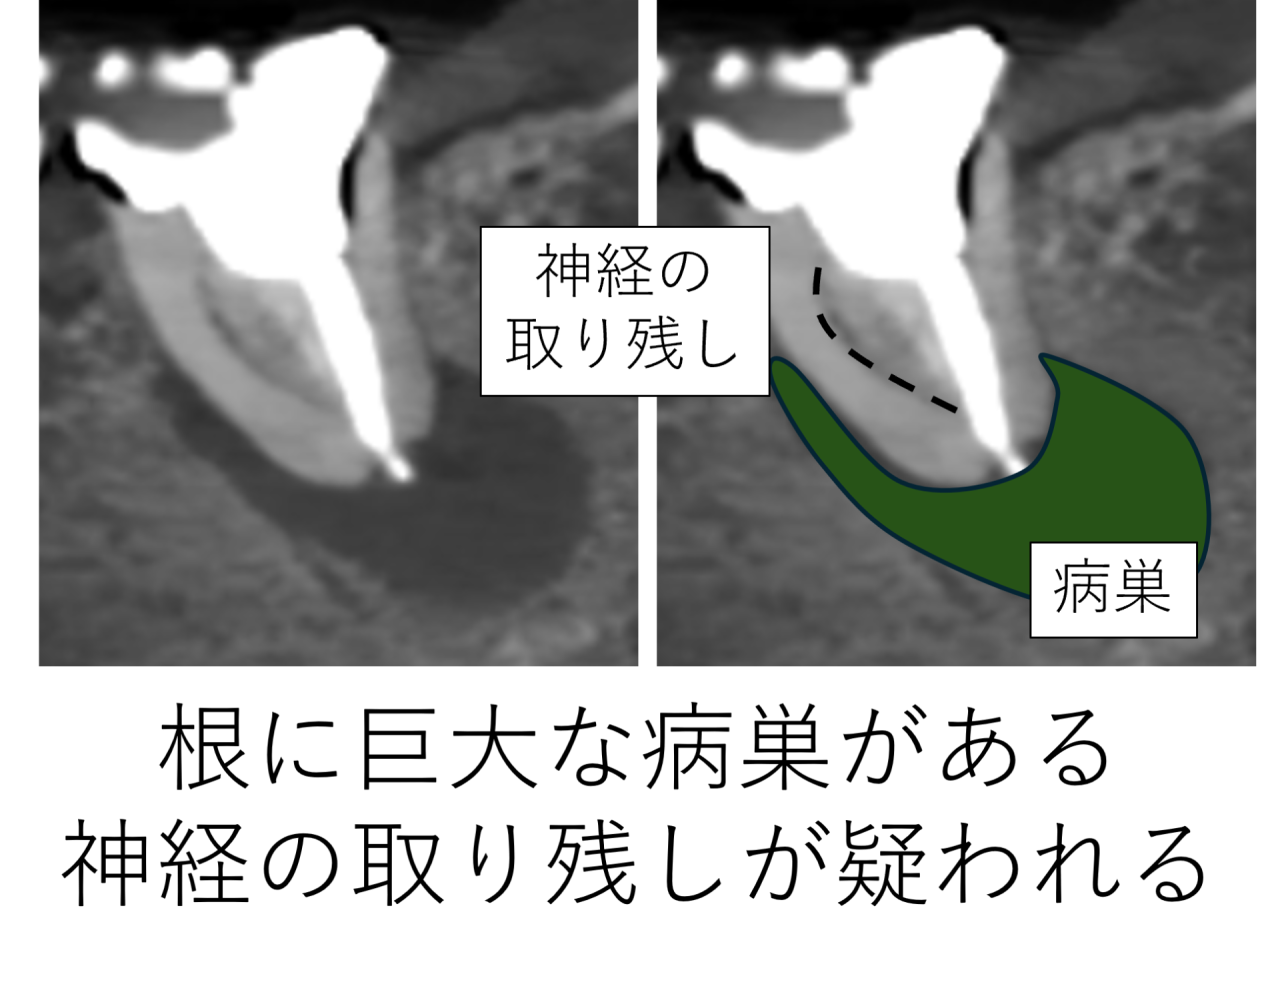

今回の症例では、詳しく調べてみると、神経がまるまる1つ取り残されていました。取り残された場合、存在する細菌の数は5億以上ともいわれます。そして、その部分を中心に感染が進み、根の先には大きな根尖病巣ができていました。

取り残されていた神経を発見し、除去しました。また神経どうしの間に溝(イスムス)が存在しました。そこにも細菌が存在するため、内部の感染源を取り除き、根管内を洗浄し綺麗になりました。